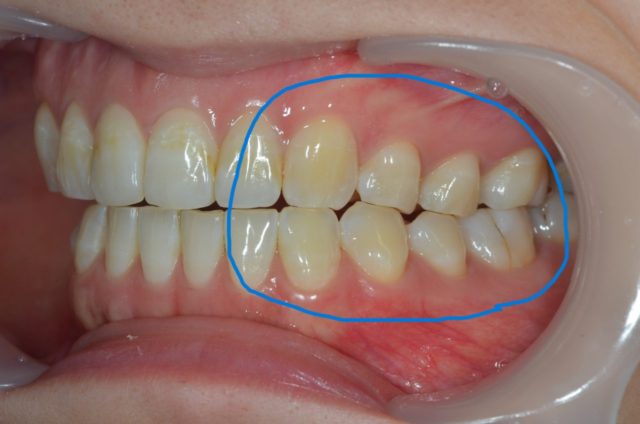

まず、私の現状としましてはこれだけ歯が減ってしまっています。

外のエナメル質という硬い組織が削れに削れ中の象牙質という組織が見えてしまっています。

見ていただくとわかるように、私はこの位置で常に寝ている時に歯ぎしりをしているようです。